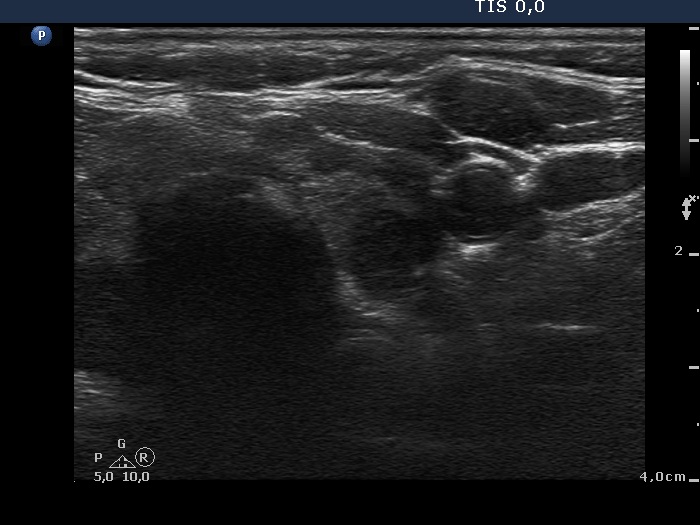

Follow-up examination 5 years later (third row of images):

Clinical presentation: the replacement therapy had been stopped for two years because the patient's cardiologist suspected the levo-tiroxine treatment worsening hypertension.

Functional state: euthyroidism (TSH 4.08 mIU/L).

Ultrasonography: the size, the echo pattern of the thyroid, i.e. the echogenicity index, the location of hypoechogenic fields were almost identical to that seen for 5 years.

Suggestion TSH-test every year.